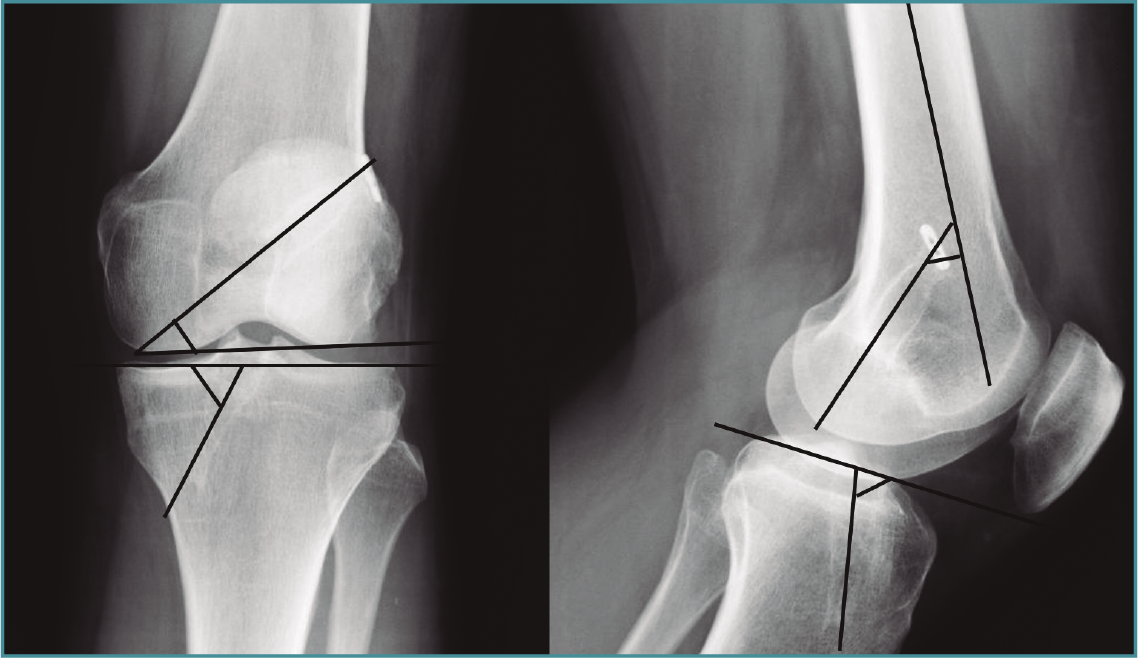

Para el cálculo de la angulación de los túneles se tuvieron en cuenta las radiografías AP y lateral de los pacientes tras un mínimo de 6 meses de seguimiento. Se trazó una línea que pasa por el centro del túnel (el eje del túnel) y a partir de esta se trazaron los ángulos:

- El ángulo del túnel femoral. En el plano coronal: es el formado por la línea del eje del túnel femoral y la línea paralela a la superficie articular femoral en la radiografía AP. En el plano sagital: es el ángulo formado por el eje del túnel y el eje de la diáfisis femoral, en la radiografía lateral.

- El ángulo del túnel tibial es el formado por la línea que pasa por el eje del túnel y por una línea paralela a la superficie articular tibial tanto en la radiografía AP como en la lateral (Figura 1).

Figura 1. Angulación del túnel femoral en plano coronal, formada por la línea del eje del túnel femoral y la línea paralela a la superficie articular femoral en la radiografía anteroposterior y, en el plano sagital, formada por el eje del túnel y el eje de la diáfisis femoral, en la radiografía lateral. El ángulo del túnel tibial es el formado por la línea que pasa por el eje del túnel y por una línea paralela a la superficie articular tibial tanto en la radiografía anteroposterior como en la lateral.